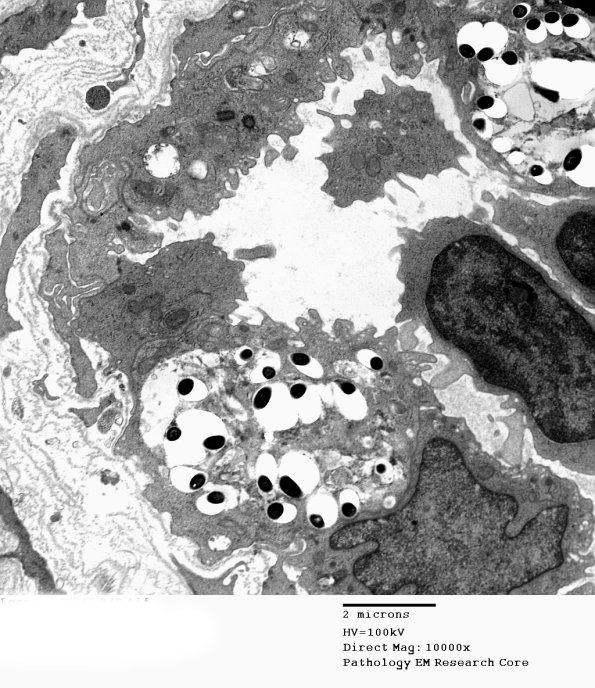

Leprous organisms infect the endothelium. Diseased endothelial cells may appear swollen, with loss of integrity of cell junctions and other signs of damage to the blood–nerve barrier. Multilayering and thickening of basement membrane around vessels is seen in all types of leprosy but it is a nonspecific finding in many chronic neuropathies. (electron micrographs)